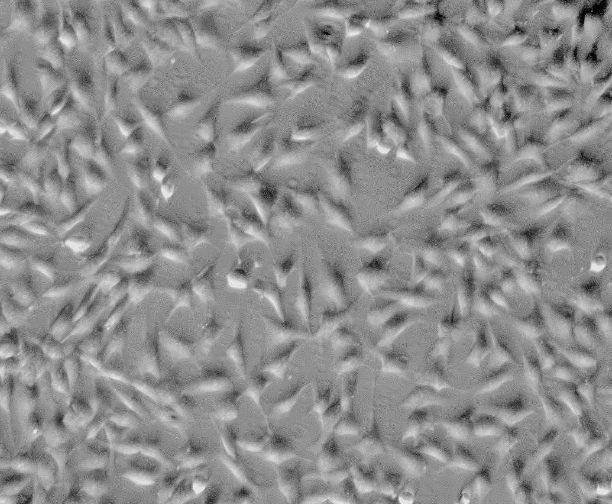

来自ScienCell研究实验室的HK从人类角膜中分离出来。HK在P0冷冻保存并冷冻。每个小瓶含有>5×10^5个细胞,1ml体积。HK的特征在于成纤维细胞形态和免疫荧光,其具有对纤连蛋白特异的抗体。HK对HIV-1,HBV,HCV,支原体,细菌,酵母和真菌均为阴性。在ScienCell研究实验室提供的条件下,HK保证进一步扩大15次人口倍增。

角膜细胞或角膜成纤维细胞是高度特化的细胞,夹在角膜基质中正交排列的胶原薄片层之间。它们在维持角膜的结构和透明度方面起着关键作用,因为它们是间质胶原蛋白和前列腺素的来源。它们在角膜伤口愈合和组织修复中也起着重要作用,并且由于生长因子和细胞因子的影响,已知它们在伤口中经历表型转化[1]。在正常条件下,成人角膜中的角膜细胞是相对静止的细胞。然而,在角膜损伤或创伤的情况下,角膜细胞分化成活性的合成细胞并迅速取代受损的基质基质。培养的人角膜细胞在细胞表面表达功能性IL-4Rs [2]和IL-17R [3],表明这些细胞可能有助于IL-4和IL-17作为角膜过敏反应的介质。在白细胞介素-1处理后在角膜细胞中观察到基因表达的变化,这提供了对基因表达的重要见解并且提出了用于控制角膜炎症的新治疗靶标。